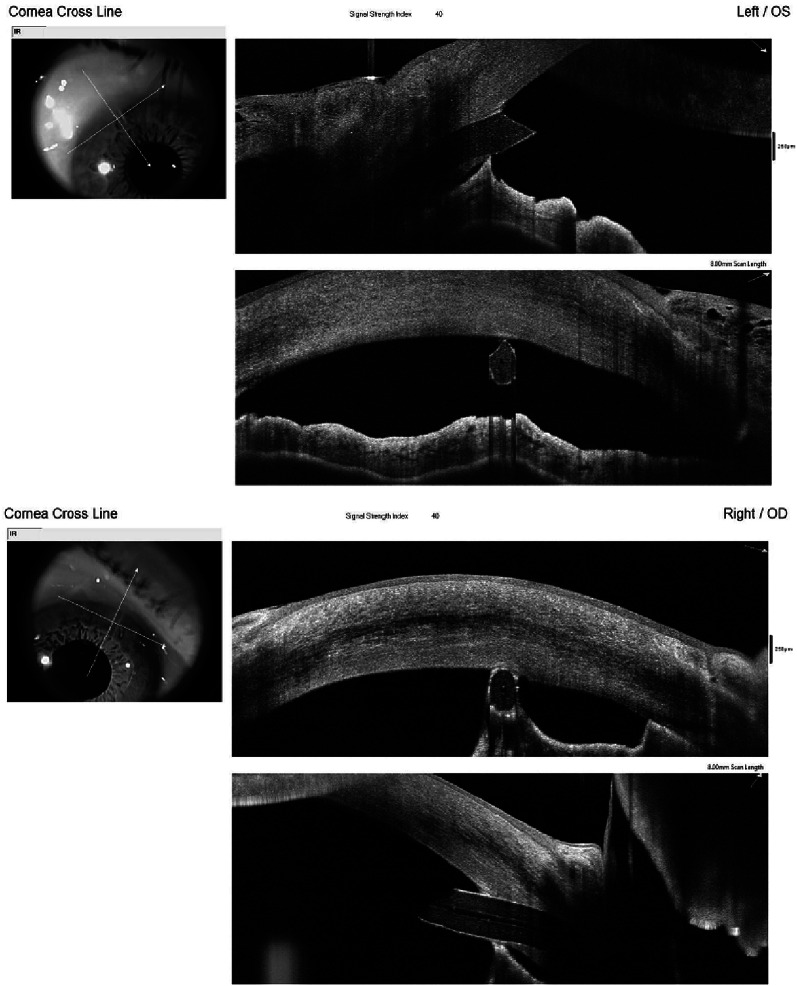

The length of the tube in the AC was measured from the beveled tip to the angle at 3 months (Fig. 1). Peripheral anterior synechiae (PAS) were evaluated by AS-OCT (Fig. 2).

Fig. 2.

AS-OCT image of two cases of peripheral anterior synechiae (PAS)